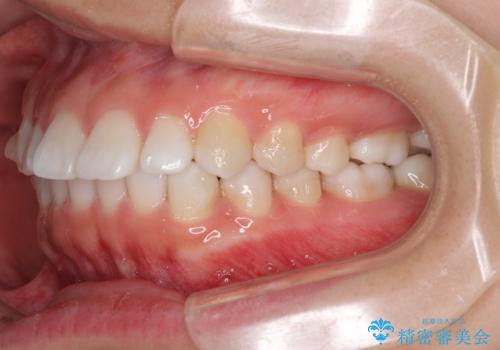

インビザラインによる軽度な出っ歯の矯正治療

- 上の前歯の出っ歯を治したいとのことで来院された患者様です。

上下顎ともにIPR(歯と歯の間を削る)と歯列全体の拡大によって口元が引っ込むように設計し、インビザラインにより治療を行うこととしました。

どこまで口元を引っ込めることができるのか、患者様自身も正直分からない部分があったため、少しずつ治療ゴールを変更しながら仕上げていきました。

気になっていた前歯の飛び出した印象は、最終的にはスッキリと引っ込み、大変満足していただきました。